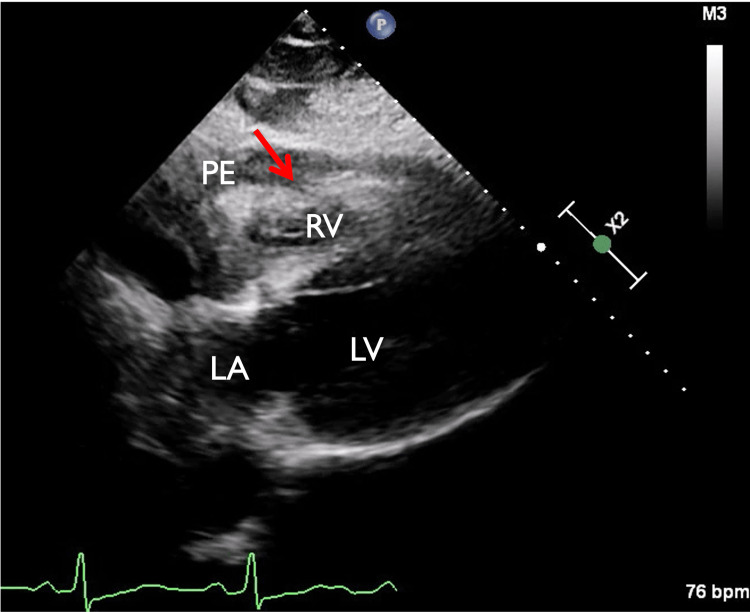

In view of chest pain associated with positive cardiac biomarkers, he was admitted to the Coronary Care Unit on intravenous nitroglycerin. While waiting for his admission, he suddenly had recurrent chest pain associated with marked hypotension (75/43 mmHg), for which the intravenous nitroglycerin was discontinued, fluid resuscitation was provided, and he was temporarily started on intravenous norepinephrine. The on-call cardiology team was contacted for an emergent evaluation. Subsequent ECG showed nonspecific ST-segment changes in leads V5-V6 (Figure 1). An emergent bedside echocardiogram revealed a moderate pericardial effusion of hemodynamic significance (Figure 2), as suggested by partial right ventricular chamber collapse (Figure 3) early in diastole and a plethoric non-collapsing inferior vena cava. The pericardial effusion also contained echogenic strands, which are highly concerning for blood clots. Additionally, a moderate to severe aortic valve insufficiency (Figure 4) was present according to color Doppler findings and pressure half-time assessment (315 ms). An intimal flap was visualized on the ascending and descending aorta, suggesting an extensive AD (Figures 2–6). A computer tomographic angiogram (CTA) of the chest and abdomen revealed a large pericardial effusion with an extensive AD extending from the level of the ascending aorta into his right brachiocephalic artery, the right and left common carotid arteries, and inferiorly to the right iliac artery (Figures 7–10), although not occlusive in diameter (or clinically). These findings were consistent with an extensive Stanford type-A AD with rupture into the pericardium, for which volume expansion and vasopressors were provided and emergently operated on the same day. The surgery included an open pericardiotomy with pericardial blood drainage, replacement of the ascending aorta from just above the commissure to the take-off of the innominate artery, partial replacement of the aortic arch, and aortic valve repair with successful results. Multiple intraoperative packed red blood cell units (8), fresh frozen plasma units (4), cryoprecipitate units (10), and platelet apheresis (3) were provided in view of bleeding complications related to the arrival provision of dual antiplatelet and anticoagulation therapy prior to the diagnosis of AD.